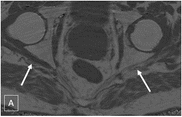

Fig. 3

63-year-old with right buttock pain and sciatica for two years, suspected piriformis syndrome. Axial T2 SPAIR (A) image shows asymmetrically hyperintense right sciatic nerve, even better identified on diffusion image (B). On mDixon quant image (C), notice increased fat fraction of the right sciatic nerve vs left (31.5% vs 27.6%) as well as increased nerve area (0.27 vs 0.25cm2). (GIF 6 kb)